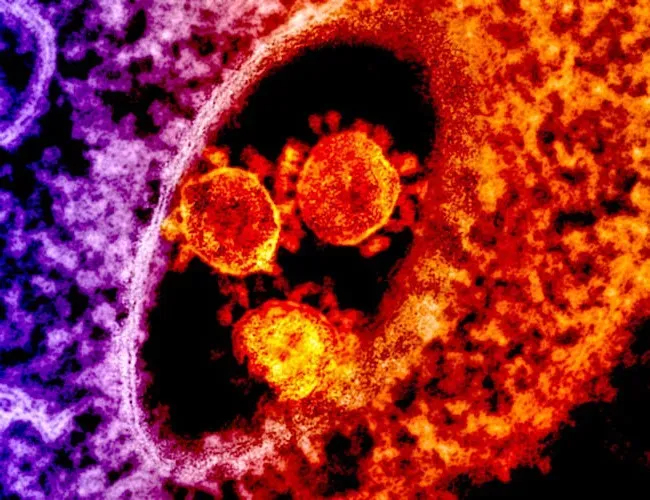

The Immune System: Your Internal Security Team

What makes this system remarkable is its ability to learn and adapt over time. After fighting off an infection, your body keeps memory cells that remain on standby, ready to respond more quickly if that same threat shows up again. Vaccines tap into this same principle by training your immune system in advance, like a rehearsal for a performance you hope never happens. When it works well, you barely notice it; when it’s overwhelmed or misdirected, you suddenly understand how much you were relying on it the whole time.